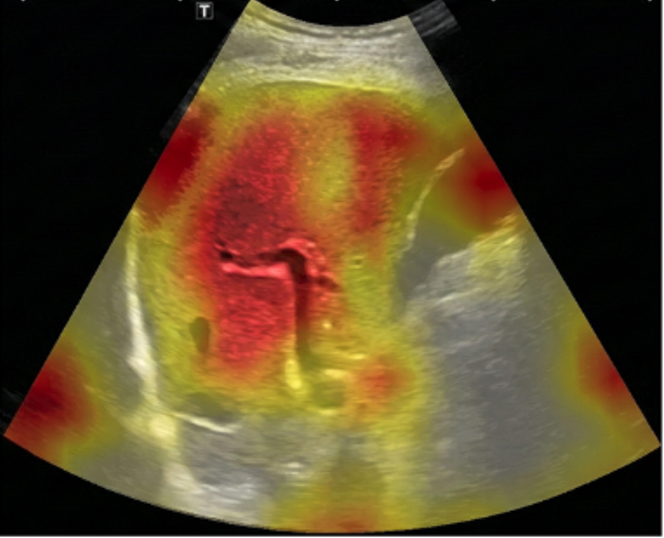

SmartLiva ทำงานเหมือน “อัปเกรด” จากภาพอัลตราซาวด์ขาวดำธรรมดาให้กลายเป็นผลวินิจฉัยที่อ่านง่ายและแม่นยำ โดยอัปโหลดภาพผ่านเว็บได้ทั้งบนคอมพิวเตอร์หรือแท็บเล็ต จากนั้นระบบจะช่วยปรับภาพให้ชัดขึ้น คัดเฉพาะบริเวณเนื้อตับที่ต้องวิเคราะห์ และทำให้ภาพดูเข้าใจง่ายขึ้นด้วยการไฮไลต์เป็นสี (เช่น ตับเป็นสีแดง ไขมันเป็นสีเหลือง) เพื่อให้เห็นความผิดปกติได้ทันที โดย AI จะทำการประเมิน 3 เรื่องพร้อมกัน คือ ประเมินระดับพังผืด/ความแข็งของตับ (F0–F4), ตรวจหาความผิดปกติของเนื้อเยื่ออย่างถุงน้ำหรือมะเร็งตับ และตรวจหาพยาธิใบไม้ตับ ซึ่งตัว AI จะทำการประมวล วิเคราะห์ และสรุปผลออกมาเป็นรายงานพร้อมภาพประกอบและคำอธิบายที่คนทั่วไปเข้าใจได้